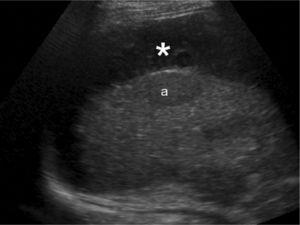

Hallazgos de imagenEn la ecografía se apreciaban múltiples lesiones hepáticas de baja ecogenicidad (fig. 1), sin flujo detectable en el estudio Doppler, y una imagen hipoecoica perihepática, con ecos internos, que se orientó como hematoma (fig. 2). En la RM algunas de las lesiones mostraban elevada intensidad en secuencias potenciadas en T1 y todas brillaban en secuencias potenciadas en T2, con realce inespecífico (fig. 3). El hematoma se comportaba de forma heterogénea aunque era hiperintenso en todas las secuencias (fig. 4).

El aspecto radiológico de estas lesiones varía en función de la cantidad de sangre no coagulada que hay en ellas y su flujo. Ecográficamente suelen ser hipoecoicas respecto al resto del parénquima, excepto cuando se complican con hemorragia, mostrando entonces focos de mayor ecogenicidad.No suelen mostrar flujo en el estudio Doppler. En la TC son lesiones hipoatenuantes, aunque pueden presentar densidad aumentada si han sangrado o mostrar calcificaciones en su interior4. Si las cavidades pelióticas son menores de 1cm el estudio puede ser normal. Como presentación inusual pueden tener niveles líquido-líquido por sangrado5. Su comportamiento tras la inyección de contraste es variable. Clásicamente se ha descrito el «signo de la diana» que consiste en un realce nodular central en fase arterial, que sigue un sentido centrífugo en fases posteriores6. En general, pueden o no tener realce progresivo y éste ser centrífugo o centrípeto7. En RM los hallazgos visualizados también varían según la edad y fase de sangrado de las lesiones, lo que traduce su variable aspecto en T1. En secuencias potenciadas en T2 son de intensidad elevada8. En la difusión, los valores de ADC de las lesiones son menores que en el parénquima sano, probablemente debido a la presencia de trombosis y hemorragia5.